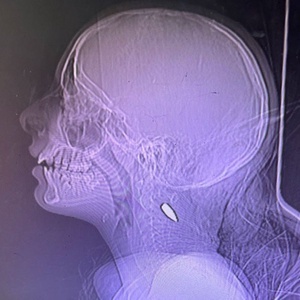

پزشکان خارجی در غزه عکس اشعه ایکس کودکانی را منتشر کردند که تک تیراندازان اسرائیلی عمداً با 5.56 گلوله توسط تروریست های اسرائیلی به سر و گردن شلیک کردند.